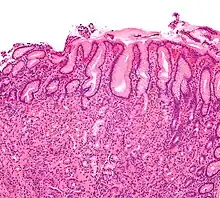

Metaplasia

Mucous gland metaplasia, the reversible replacement of differentiated cells, occurs in the setting of severe damage of the gastric glands, which then waste away (atrophic gastritis) and are progressively replaced by mucous glands. Gastric ulcers may develop; it is unclear if they are the causes or the consequences. Intestinal metaplasia typically begins in response to chronic mucosal injury in the antrum and may extend to the body. Gastric mucosa cells change to resemble intestinal mucosa and may even assume absorptive characteristics. Intestinal metaplasia is classified histologically as complete or incomplete. With complete metaplasia, gastric mucosa is completely transformed into small-bowel mucosa, both histologically and functionally, with the ability to absorb nutrients and secrete peptides. In incomplete metaplasia, the epithelium assumes a histologic appearance closer to that of the large intestine and frequently exhibits dysplasia.[20]